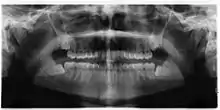

Impacted wisdom teeth are classified by their direction of impaction, their depth compared to the biting surface of adjacent teeth and the amount of the tooth's crown that extends through gum tissue or bone. Impacted wisdom teeth can also be classified by the presence or absence of symptoms and disease. Screening for the presence of wisdom teeth often begins in late adolescence when a partially developed tooth may become impacted. Screening commonly includes a clinical examination as well as x-rays such as panoramic radiographs.

The diagnosis of impaction can be made clinically if enough of the wisdom tooth is visible to determine its angulation, depth, and if the patient is old enough that further eruption or uprighting is unlikely. Wisdom teeth continue to move to the age of 25 years old due to eruption, and then continue some later movement owing to periodontal disease.[18]

If the tooth cannot be assessed with clinical exam alone, the diagnosis is made using either a panoramic radiograph or cone-beam CT. Where unerupted wisdom teeth still have eruption potential several predictors are used to determine the chance of the teeth becoming impacted. The ratio of space between the tooth crown length and the amount of space available, the angle of the teeth compared to the other teeth are the two most commonly used predictors, with the space ratio being the most accurate. Despite the capacity for movement into early adulthood, the likelihood that the tooth will become impacted can be predicted when the ratio of space available to the length of the crown of the tooth is under 1.[5]:141